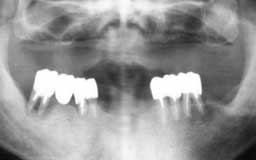

Hさん 初診時 53歳 男性

50歳頃まではもう少し歯があったそうですが、歯科医院に行くたびに「歯槽膿漏です」といわ れて抜歯。60歳まで何とか総入れ歯にしたくないという

Hさん 19年後 72歳

上顎の補綴処置と左下の親知らずを抜歯。歯槽膿漏の手術を行うことなく月に1度の歯石除去 を継続して行った結果、初診時から大きく変化することなく19年を経過しました